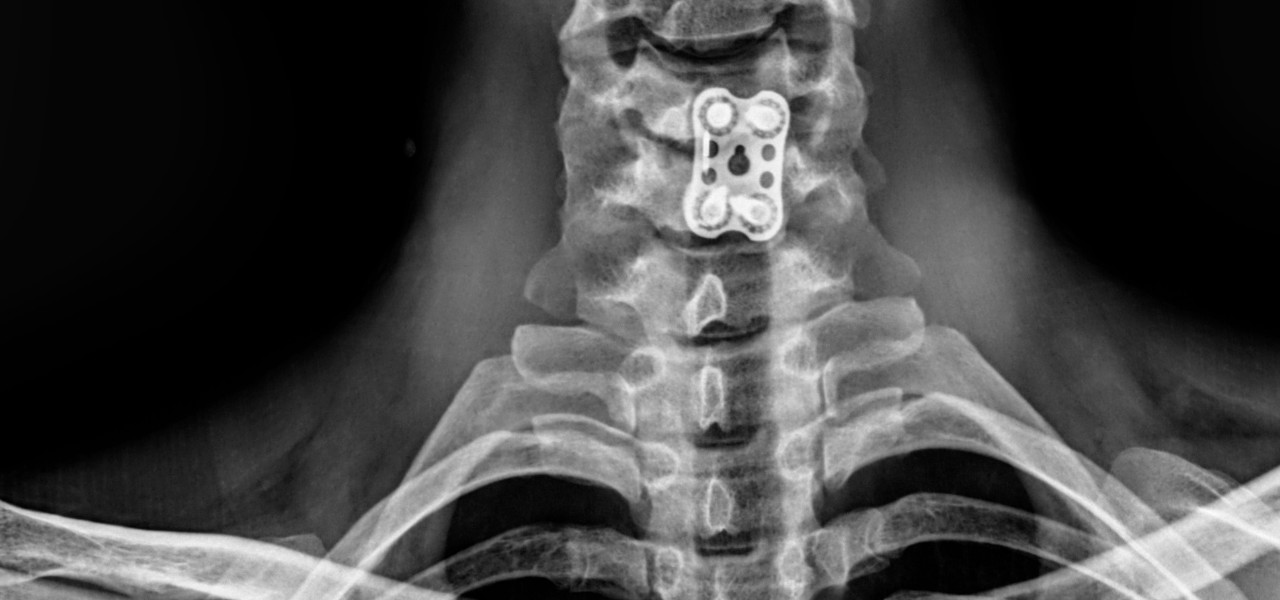

Humanos

• Niños

• Adultos

• Pacientes geriatras

• Seguimiento post cirugía ortopédica

HumanosRadiología Digital Directa

Posteriormente la radiología computarizada evolucionó a la radiología digital directa en donde podíamos hacer placas radiográficas y ver las imágenes en aproximadamente 18-20 segundos después de tomar la radiografía, y esto fue un gran avance para la comunidad de médicos, veterinarios, antropólogos, restauradores, paleontólogos, investigadores, y gente que requería radiografías y que por la logística que se requería y lo que implicaba no utilizaba esta herramienta de diagnóstico. En la actualidad, en la era de la inmediateidad podemos tomar placas radiográficas de alta definición en 2-3 segundos, en lugares remotos, sin necesidad de energia electrica ya que los generadores de rayos X funcionan con baterías, así como los equipos de radiología digital directa, esto ha permitido que el servicio de radiología se pueda proporcionar en cualquier lugar donde se requiera, pudiendo llevarse a donde están los pacientes u objetos a radiografiar, con las ventajas que esto implica. Los equipos actuales son ligeros, portátiles, de alta frecuencia, de alta definición, se ha optimizado la radiación que generan, lo que permite obtener imágenes radiográficas de muy buena calidad, con técnicas radiográficas inferiores a lo que se requería con radiología análoga. Hoy en día manejamos radiología digital directa de alta resolución.

Ideal para pacientes con incapacidad para trasladarse al hospital o moverse. Fracturados, con fijación externa, osteoporosis, niños, adultos, pacientes geriatras, seguimiento post cirugía ortopédica.